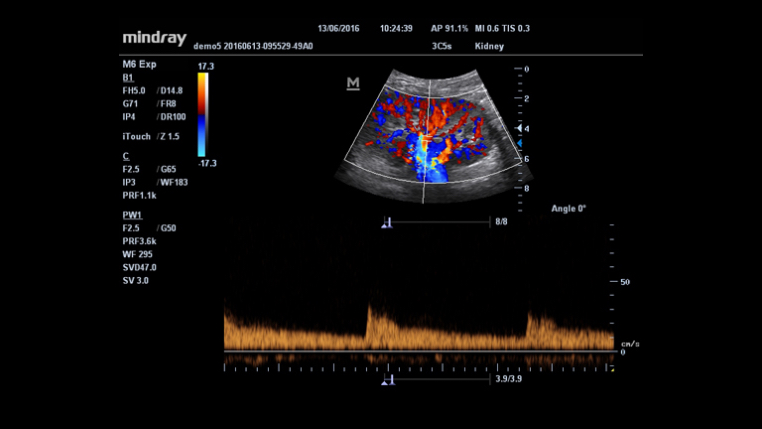

An innovative technology to better visualize tiny vessels and complex flow patterns, based on Mindray's exclusive processing algorithm.

iTouch? (Auto Image Optimization)

Gain instant auto image optimization in B, Color and PW Modes on the click of single key.

Smart Track

MindrayŌĆÖs unique function: Continuously track the color flow and optimize the best Color box position and angle in real time scanning